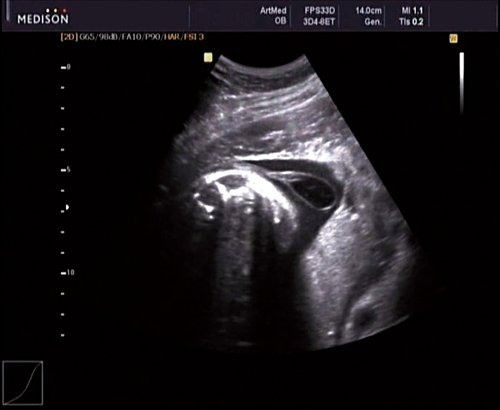

Беременная М., 21 года. Впервые обратилась в клинику в срок 20 нед беременности. Исследование проводилось на аппарате SonoAce-R7 (Samsung Medison) с использованием режима поверхностной объемной реконструкции 3D/4D. При изучении позвоночника плода в трех плоскостях костных деформаций не выявлено. В грудном отделе позвоночника обнаружено тонкостенное кистозное образование с анэхогенным содержимым, стебельчатой формы (рис. 10-12). Степень "прозрачности" содержимого была выше околоплодных вод, что позволяло идентифицировать его как ликвор. В проекции грыжевого выпячивания располагалась петля пуповины, дифференциальную диагностику которой без труда удалось провести с помощью ЦДК (рис. 13).

Рис. 10. Беременность 20 нед. Менингоцеле: типичное кистозное образование стебельчатой формы.

Рис. 11. Беременность 20 нед. Менингоцеле.

Рис. 12. Менингоцеле. В сагиттальном срезе видна неровность кожи в проекции расщелины.